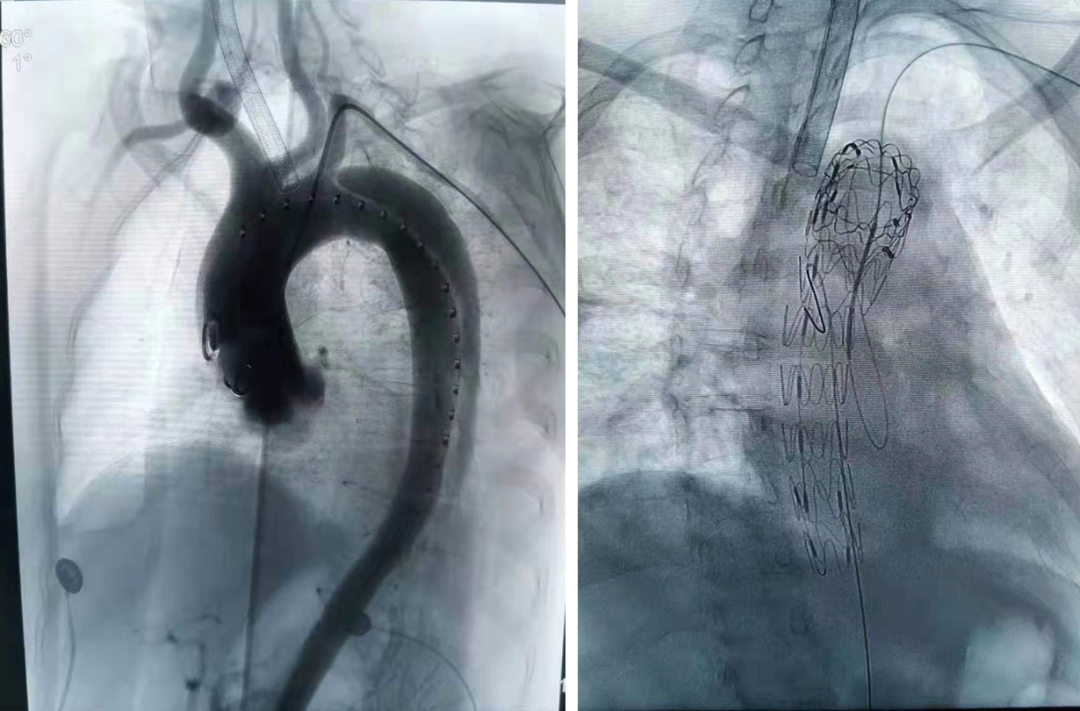

全麻下双上肢穿刺,右股动脉切开,左上肢路径造影,右上肢进保护性导丝,对支架预开窗后植入升主,因破口较大,支架近端掉入破口,远端扭转遮蔽左颈总动脉及头臂干,窗口对破口,再次植入一枚38-80支架,封住近端破口后,以8*60支架开放右侧头臂干,6*10人工血管行右锁骨下-左颈总搭桥,取颈前静脉行左椎动脉-人工血管搭桥,之后造影,头臂动脉均通常,术后约2小时患者清醒。

后释放支架预开窗病例